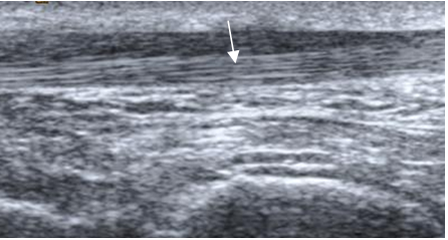

Los tendones también se aprecian como estructuras ovaladas, con baja SI en todas las secuencias. (1).

El tendón de Aquiles es el mas fuerte del cuerpo y está conformado por los músculos soleo, gastrognemio medial y lateral. Tiene una zona hipovascular entre 4 y 6 cm antes de su inserción, donde se produce la mayoría de lesiones. (2).

La parte anterior del tendón es plana o levemente cóncava, en los cortes axiales (2) y es mejor estudiado en las secuencias sagitales. (1). Presenta con algunas áreas con SI intermedia en T1 y DP, que corresponden a vasos o septos (2) y en ocasiones mínima cantidad de líquido se encuentra en la vaina del tendón, que no es clínicamente significativa. (1). (Fig 22, 23 y 24).

Fig 22. Tendón de aquiles normal en ecografía, corte sagital.

A: Tercio medio y B: En su inserción.

Fig 23. Tendón de aquiles normal.

A: Ecografía transversa y B: RM axial en T1. Estructura ovalada y homogénea, cóncava anteriormente. En RM hay zonas hiperintensas, que corresponden a septos.

Fig 24. Tendón de aquiles normal.

RM sagital en T1. Estructura lineal e hipointensa en todas las secuencias.